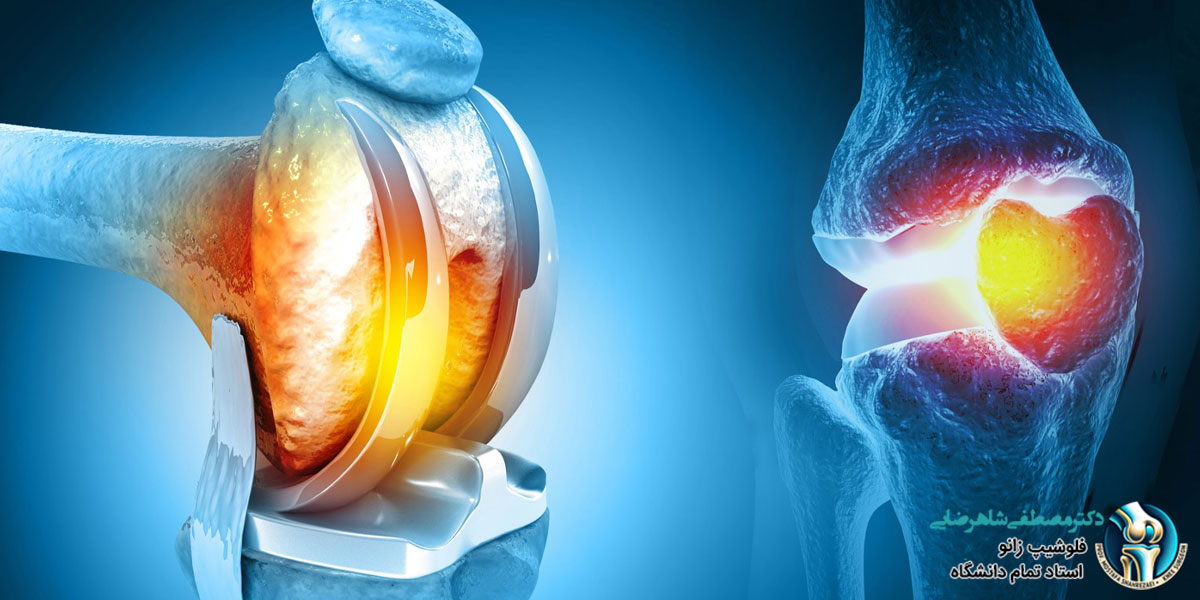

زانو یکی از پرتحرک ترین مفاصل بدن انسان است که با گذشت زمان و تحت فشارهای مکرر دچار ساییدگی و آسیب می شود. این آسیب ها می توانند در طول زمان منجر به درد شدید، محدودیت حرکت و کاهش کیفیت زندگی فرد شوند. یکی از راه حل های درمانی برای مشکلات شدید زانو، جراحی تعویض مفصل زانو است. با این حال، در بسیاری از موارد نیازی به تعویض کامل مفصل نیست و تنها تعویض جزئی آن کافی است. در این مقاله به بررسی شرایطی می پردازیم که تعویض مفصل زانو به صورت جزئی انجام می شود. اگر با مشکلات زانو مواجه هستید و به دنبال مشاوره و راهنمایی هستید، می توانید به دکتر مصطفی شاهرضایی، متخصص ارتوپدی و زانو، مراجعه کنید.

تعویض مفصل زانو به صورت جزئی یا “آرتروپلاستی جزئی زانو” یک روش جراحی است که در آن تنها بخشی از مفصل زانو که آسیب دیده است، جایگزین می شود. این روش در مقایسه با تعویض کامل مفصل زانو تهاجمی کمتری دارد و معمولاً برای افرادی مناسب است که تنها یک قسمت از زانوی آن ها دچار آسیب یا تخریب شده است. در این جراحی، جراح بخش آسیب دیده مفصل را بر می دارد و آن را با یک پروتز مصنوعی جایگزین می کند، در حالی که سایر بخش های سالم زانو دست نخورده باقی می مانند.

تعویض مفصل زانو به صورت جزئی زمانی انجام می شود که تنها یک بخش از زانو دچار تخریب یا آسیب شده باشد. این روش بیشتر برای بیمارانی که دچار آرتروز موضعی یا پارگی های خاصی در زانو هستند مناسب است. از جمله شرایطی که ممکن است نیاز به تعویض مفصل زانو به صورت جزئی باشد عبارتند از: